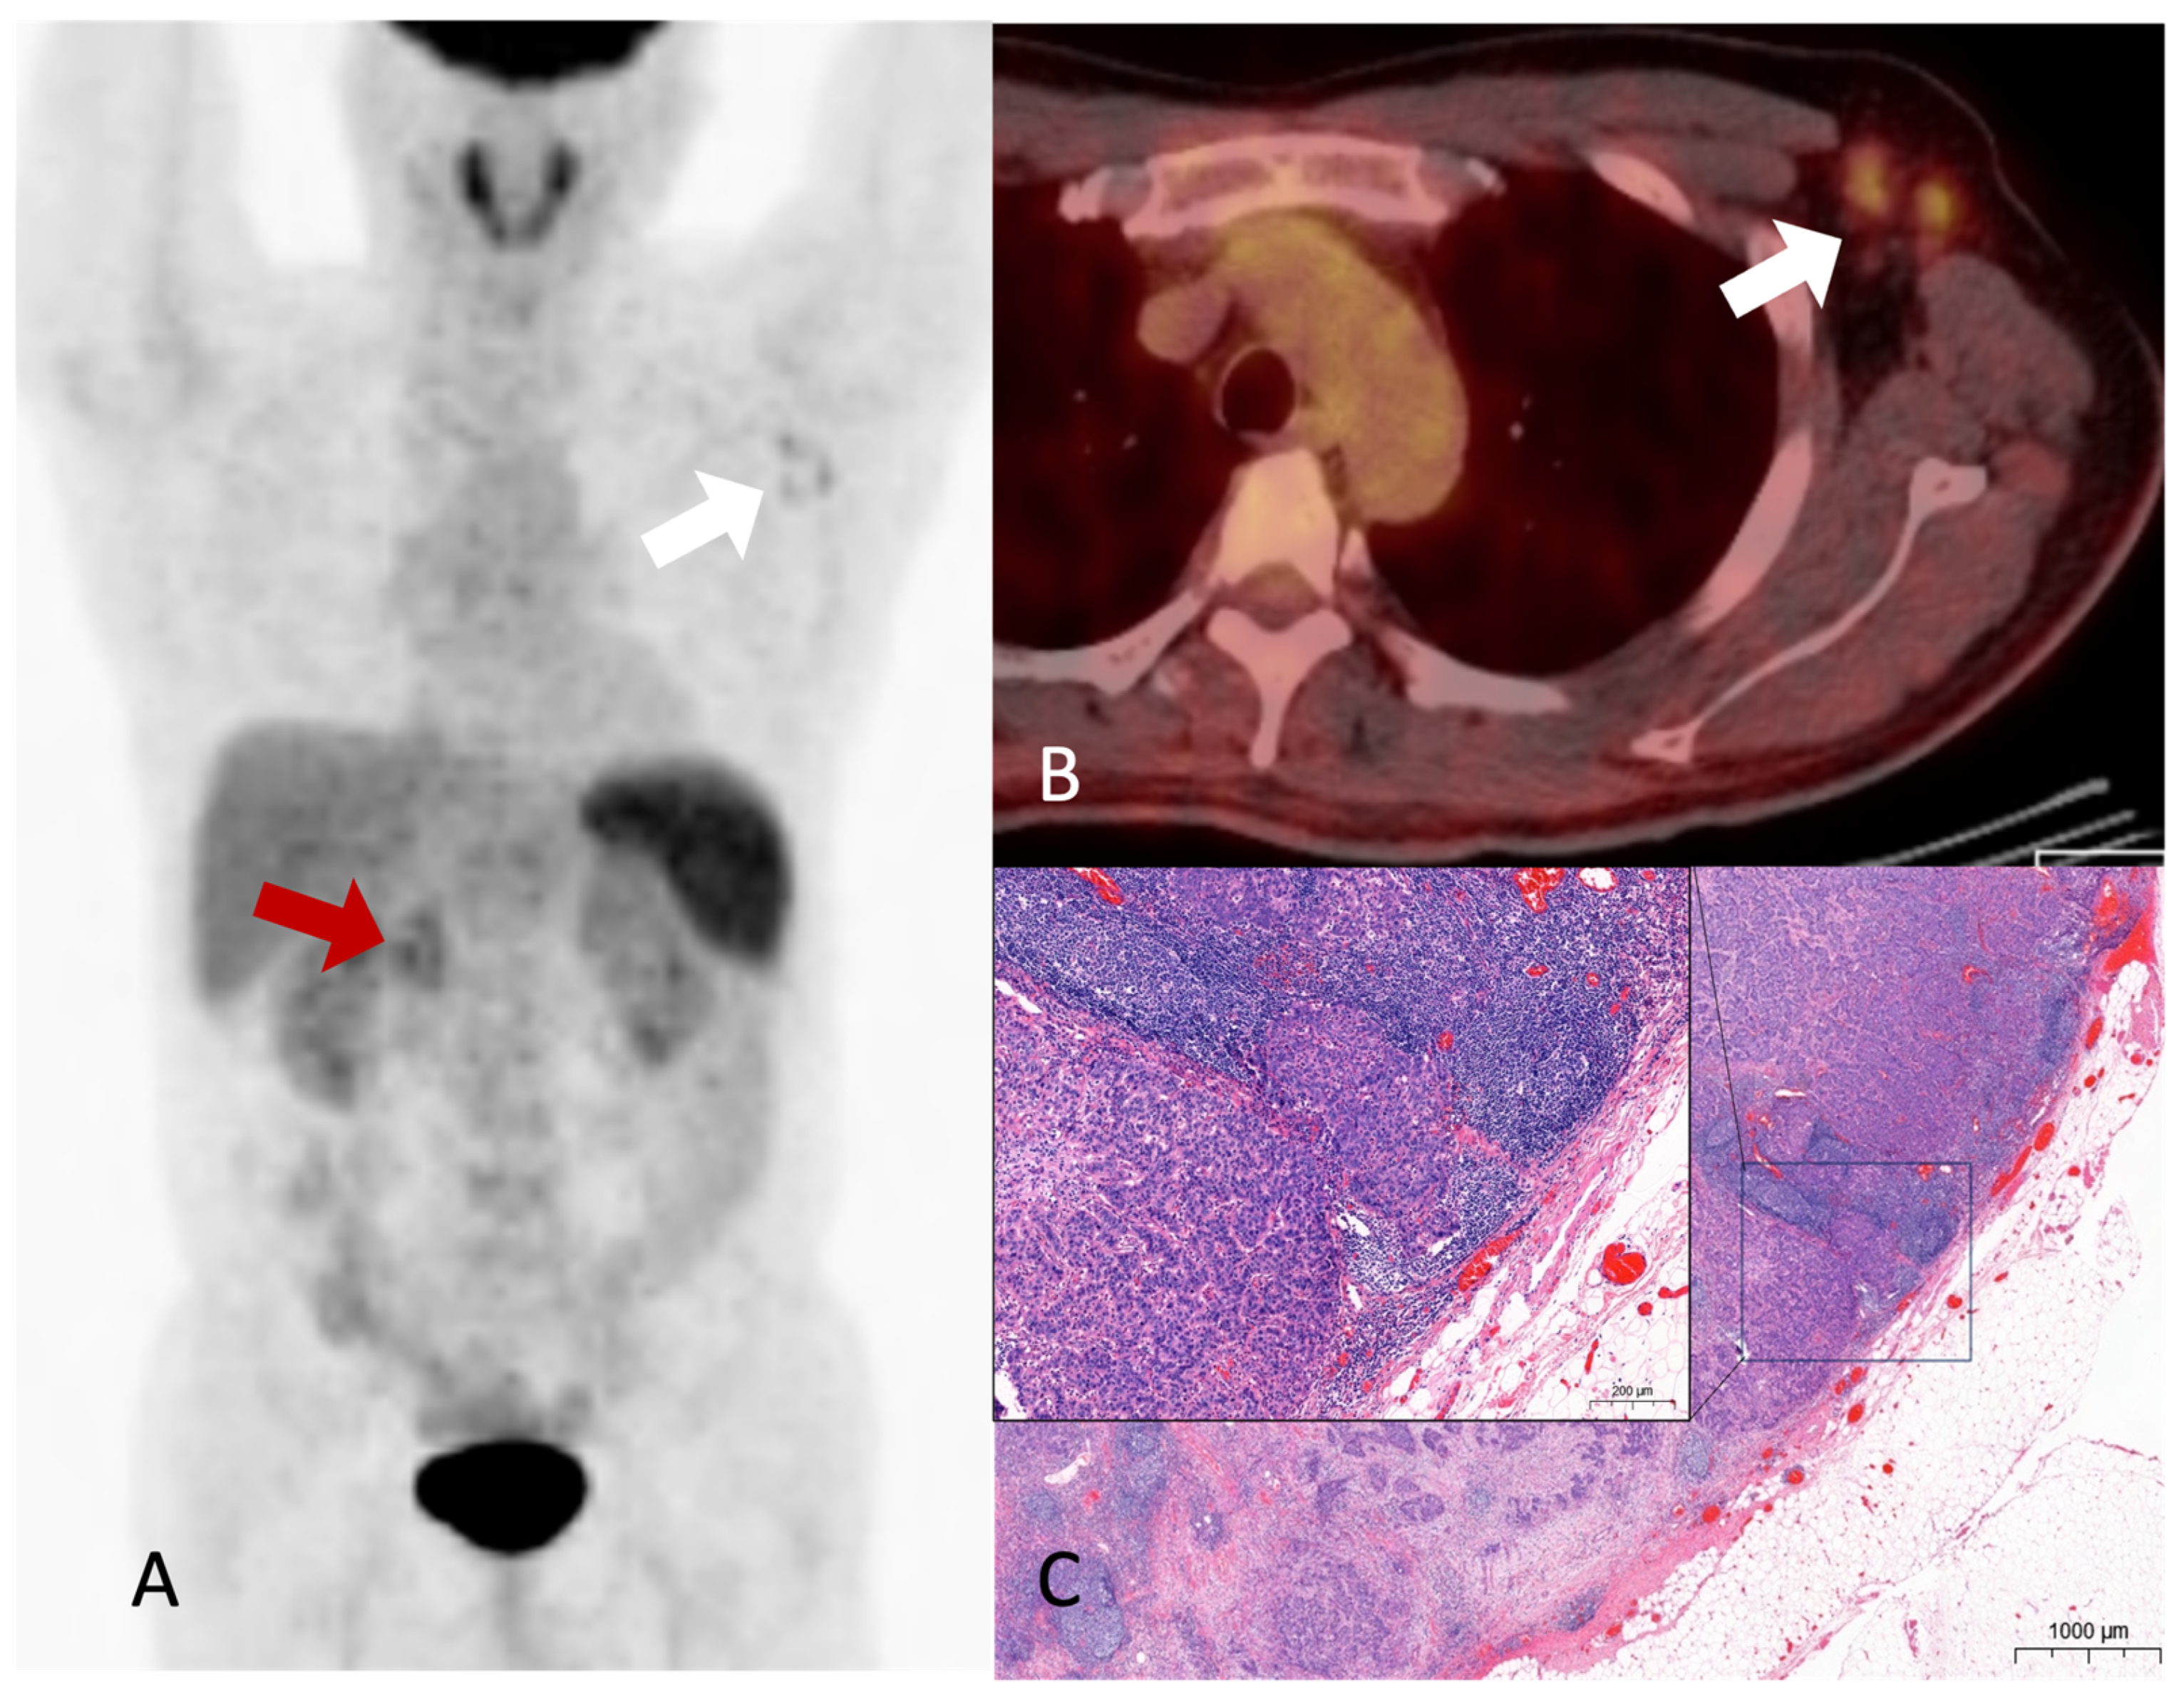

A Rare Axillary Lymph Node Metastasis on 18F-FDG PET/CT for Staging in a Patient with Common Bile Duct Cancer

Lee, Y.; Won, H.S.; Seo, K.J.; Na, S.J. A Rare Axillary Lymph Node Metastasis on 18F-FDG PET/CT for Staging in a Patient with Common Bile Duct Cancer. Diagnostics 2023, 13, 3012. https://doi.org/10.3390/diagnostics13183012